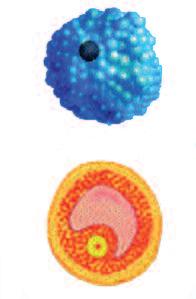

Naturalmente questi sfere, nella vita reale, sono molecole biologiche, proteine, che hanno la capacità di tagliare le fibre di collagene e di altre molecole del tessuto connettivo. L‘immagine sopra mostra che non c’è un solo tipo di 'pacman' ovvero di queste molecole, ma

Plasmin ogeni

Metal loproteinasi (MMP)

Digestione del tessut o connet tivo del tessuto connetti vo diversi tipi, quali il plasminogeno/plasmina e le metalloproteasi (strutture colorate tridimensionali). Queste molecole migliorano il loro effetto distruttivo attivandosi reciprocamente in forma di reazione a catena in cascata.